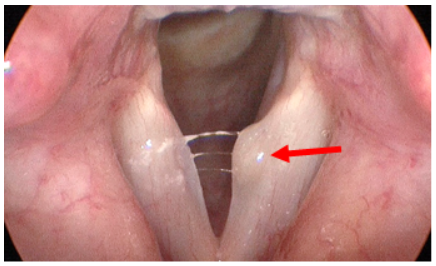

Pre- and post-operative images of a left true vocal fold cyst

Pre operative Laryngeal Microsurgery example Post operative Laryngeal Microsurgery example